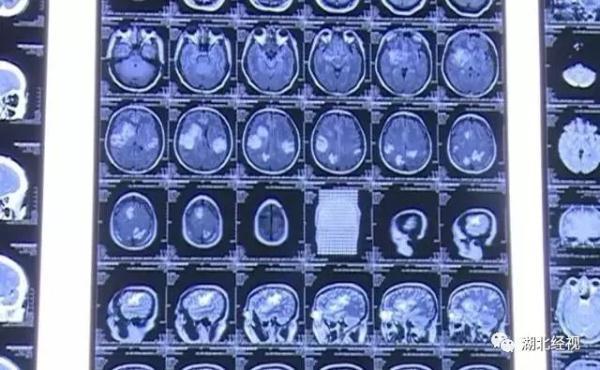

据韦先生的主治医生介绍,韦先生经过一系列检查发现,他脑子里有很多虫子爬过的痕迹,被确诊为“脑囊虫病”。脑囊虫?那韦先生的癫痫跟这些虫子有什么关系?

医生表示,由于那些虫子在脑里死亡,引起了炎症和脑水肿需要将癫痫的致痫灶切除,因为韦先生的情况比较严重,经过详细诊断之后,医生决定马上为他做手术。在医生的手术之后,韦先生正在顺利康复中,也没有出现抽搐的情况了。不过对于韦先生,脑里那些虫子的出处,我们都深感意外。这一切竟然和韦先生家乡过年的一个习俗有关。